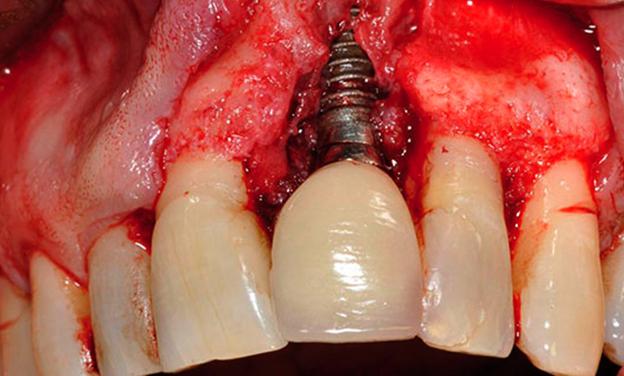

ENFERMEDADES PERIIMPLANTARIAS

enfermedad periimplantaria

Pérdida de hueso alrededor del implante

La periimplantitis se define como un proceso imflamatorio que afecta a los tejidos que rodean al implante dental y que ocasiona una pérdida del soporte óseo en el que se ha integrado. Si el problema inflamatorio afecta únicamente a los tejidos blandos, se denomina mucositis periimplantaria ( sin perdida de hueso), pero si no se trata a tiempo puede originar una periimplantitis (inflamación con pérdida de hueso). Según un estudio transversal de la Universidad de Barcelona publicado en el año 2012, la periimplantitis podría afectar hasta un 20%  de los pacientes portadores de implantes, y la mucositis hasta un 45%.